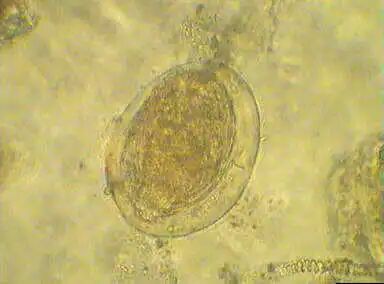

粪便中的虫卵

虫卵入水形成的毛蚴